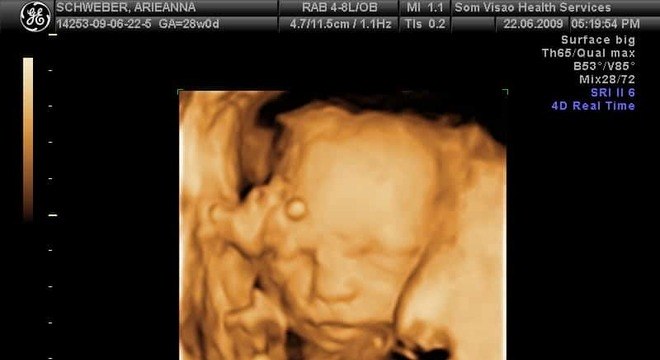

Atualmente, o ultrassom 3D é comumente utilizado para fins estéticos, como um book fotográfico do bebê e até as impressões da imagem. No entanto, a chamada imagem espacial (3D) tem aplicações específicas na obstetrícia com indicação médica, além de ser bastante utilizado em outras áreas, como a Cardiologia e Ginecologia.

“A utilidade está no diagnóstico de patologias e em medidas volumétricas com maior precisão e na maior facilidade de interpretação da imagem para as pessoas leigas ( todos conseguem entender a forma e a posição do bebê)”, explica o médico.

Com o avanço da tecnologia, outras opções ainda mais nítidas podem trazer à família uma visão mais delineada do bebê. O ultrassom 4D inclui a “dimensão tempo” no processo do exame, obtendo imagens em tempo real com maior velocidade. “Isso permite observar os movimentos fetais e imagens da superfície (pele) com maior definição, sendo possível até aos pais a identificação de características semelhantes nos pais”, diz Wagner.